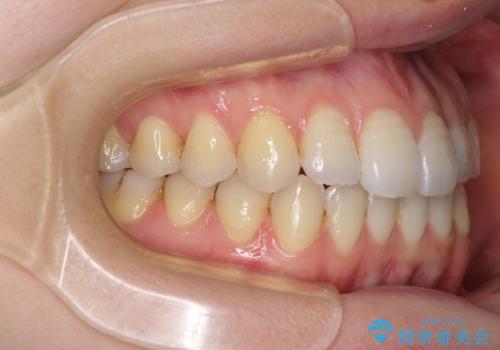

オープンバイトのインビザラインを用いた再矯正

- 矯正治療の後戻りを気にして来院された患者様です。

オープンバイト(前歯の開咬)と下顎骨の偏位による不正咬合が認められました。

骨格の偏位による不正咬合は改善しきれないことを理解いただいた上で、インビザラインにて矯正治療を行うこととしました。

オープンバイトは後戻りを起こしやすいため、極力そのリスクを軽減するため、奥歯を圧下させるように治療を進めていきました。

下顎骨の偏位が顕著であったため、上下の正中を合わせることはできませんでしたが、患者様には大変満足していただきました。